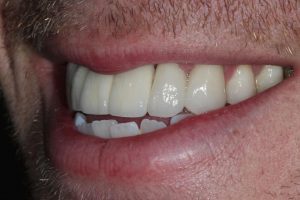

Upper Front Tooth Implant

Both upper front teeth were in a bad way, the upper left one had to be removed as was beyond repair, this was replaced with an implant and a temporary crown on the same day; the upper right front tooth was repaired with a crown. Photos show the result with the definitive crowns after 3 months of treatment.